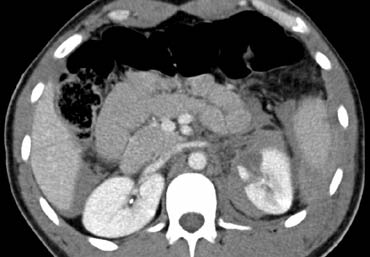

Biểu hiện phổ biến hơn của chấn thương tụy là những gì được thấy ở bên trái.

Cuộn qua các hình ảnh và mô tả các phát hiện.

Sau đó tiếp tục.

Đây là tổn thương phối hợp theo vùng bên trái điển hình.

Có chấn thương đuôi tụy kèm theo chấn thương lách, chấn thương thận và tràn khí phúc mạc.